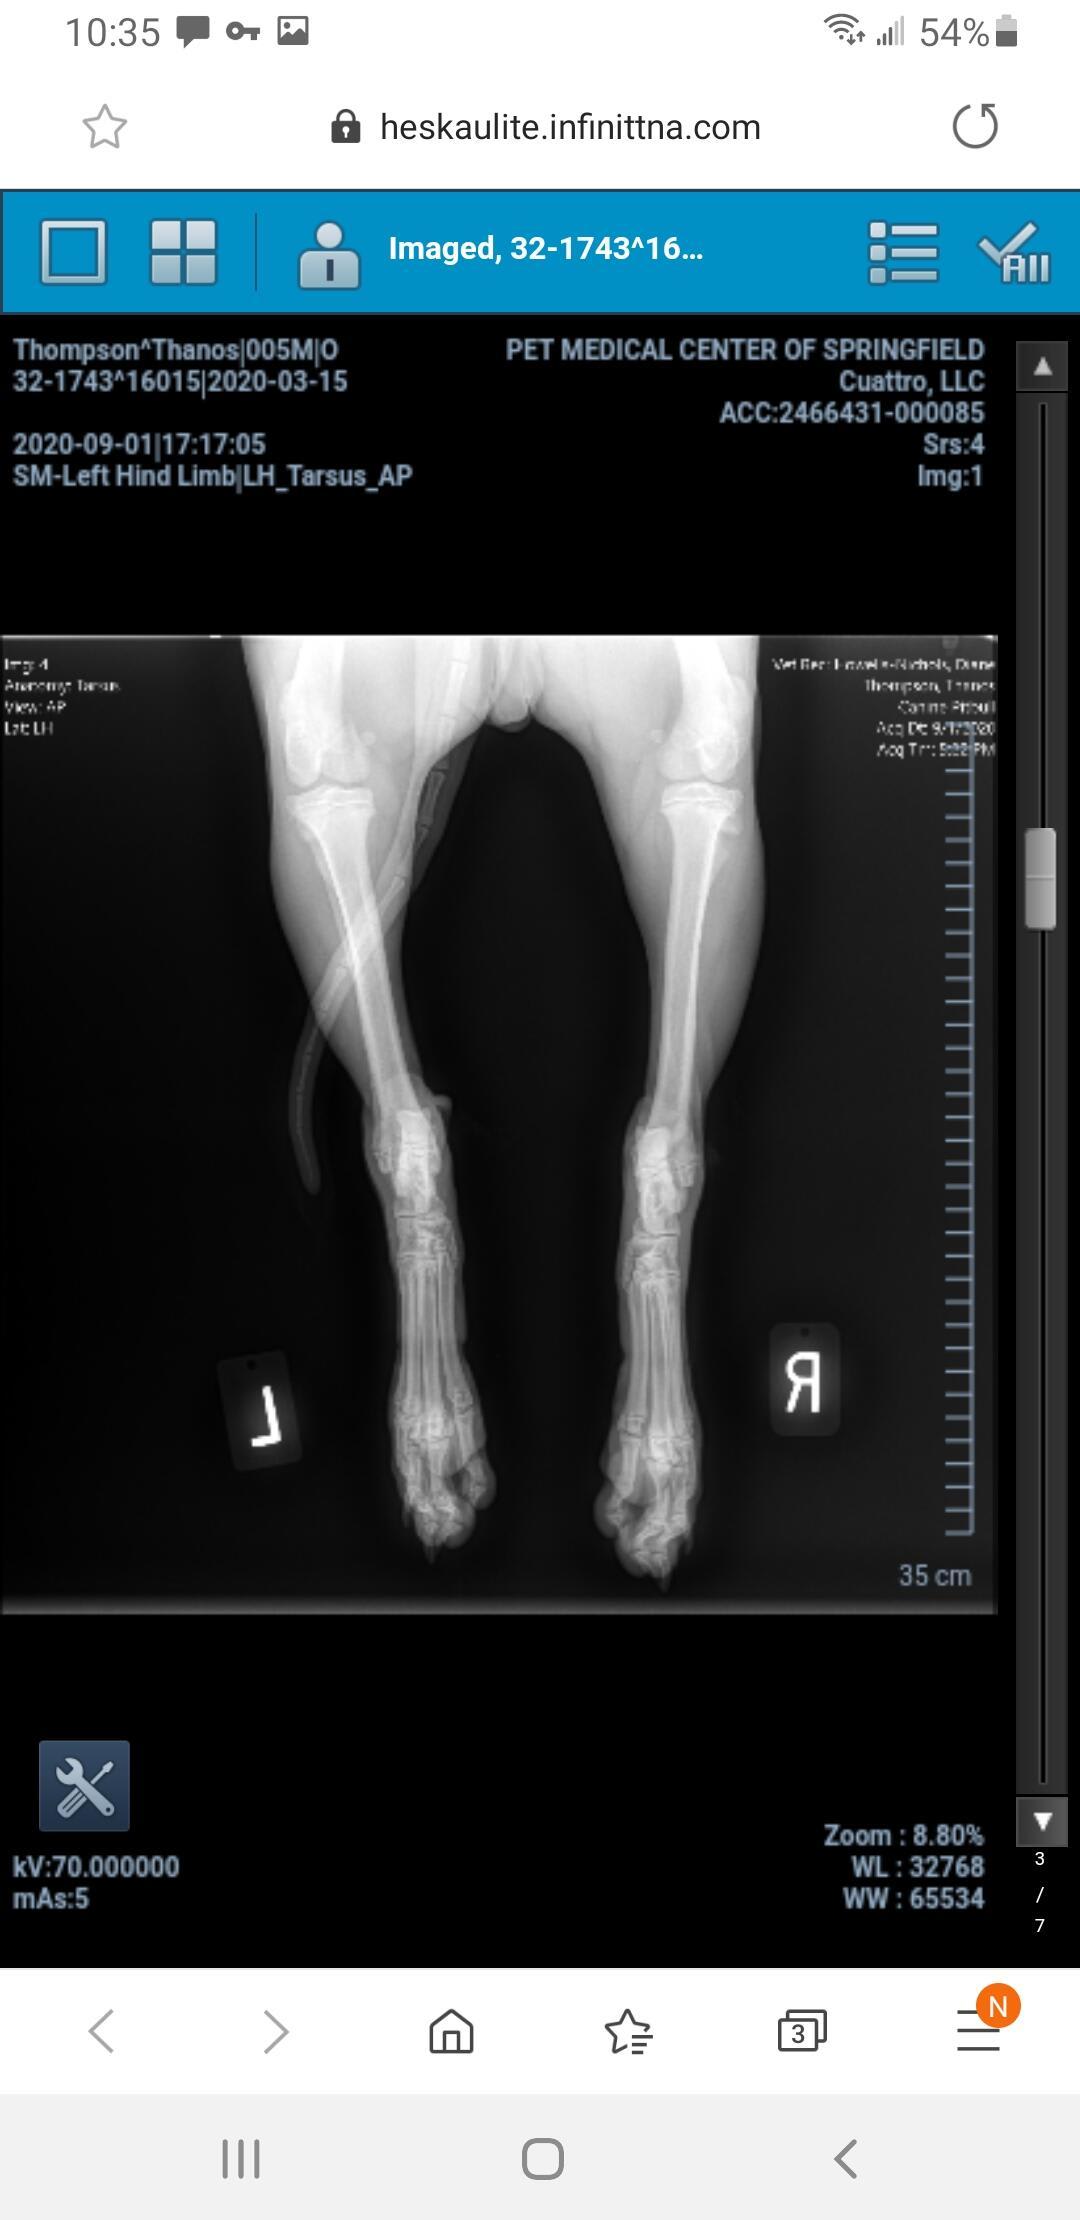

My dog jumped for a water bottle and landed wrong. Is he injured?

Pet's info: Dog | American Pit Bull Terrier | Male | unneutered | 5 months and 18 days old | 37 lbs

Dog jumped up for water bottle and landed wrong

Hello. Most likely your veterinarian recommended surgery to repair the fracture, & I would confirm that that is the best way to go. So sorry this has happened to Thanos, but glad you are looking out for him. Thanks for contacting Petco Pet Education Center, formerly Petcoach.